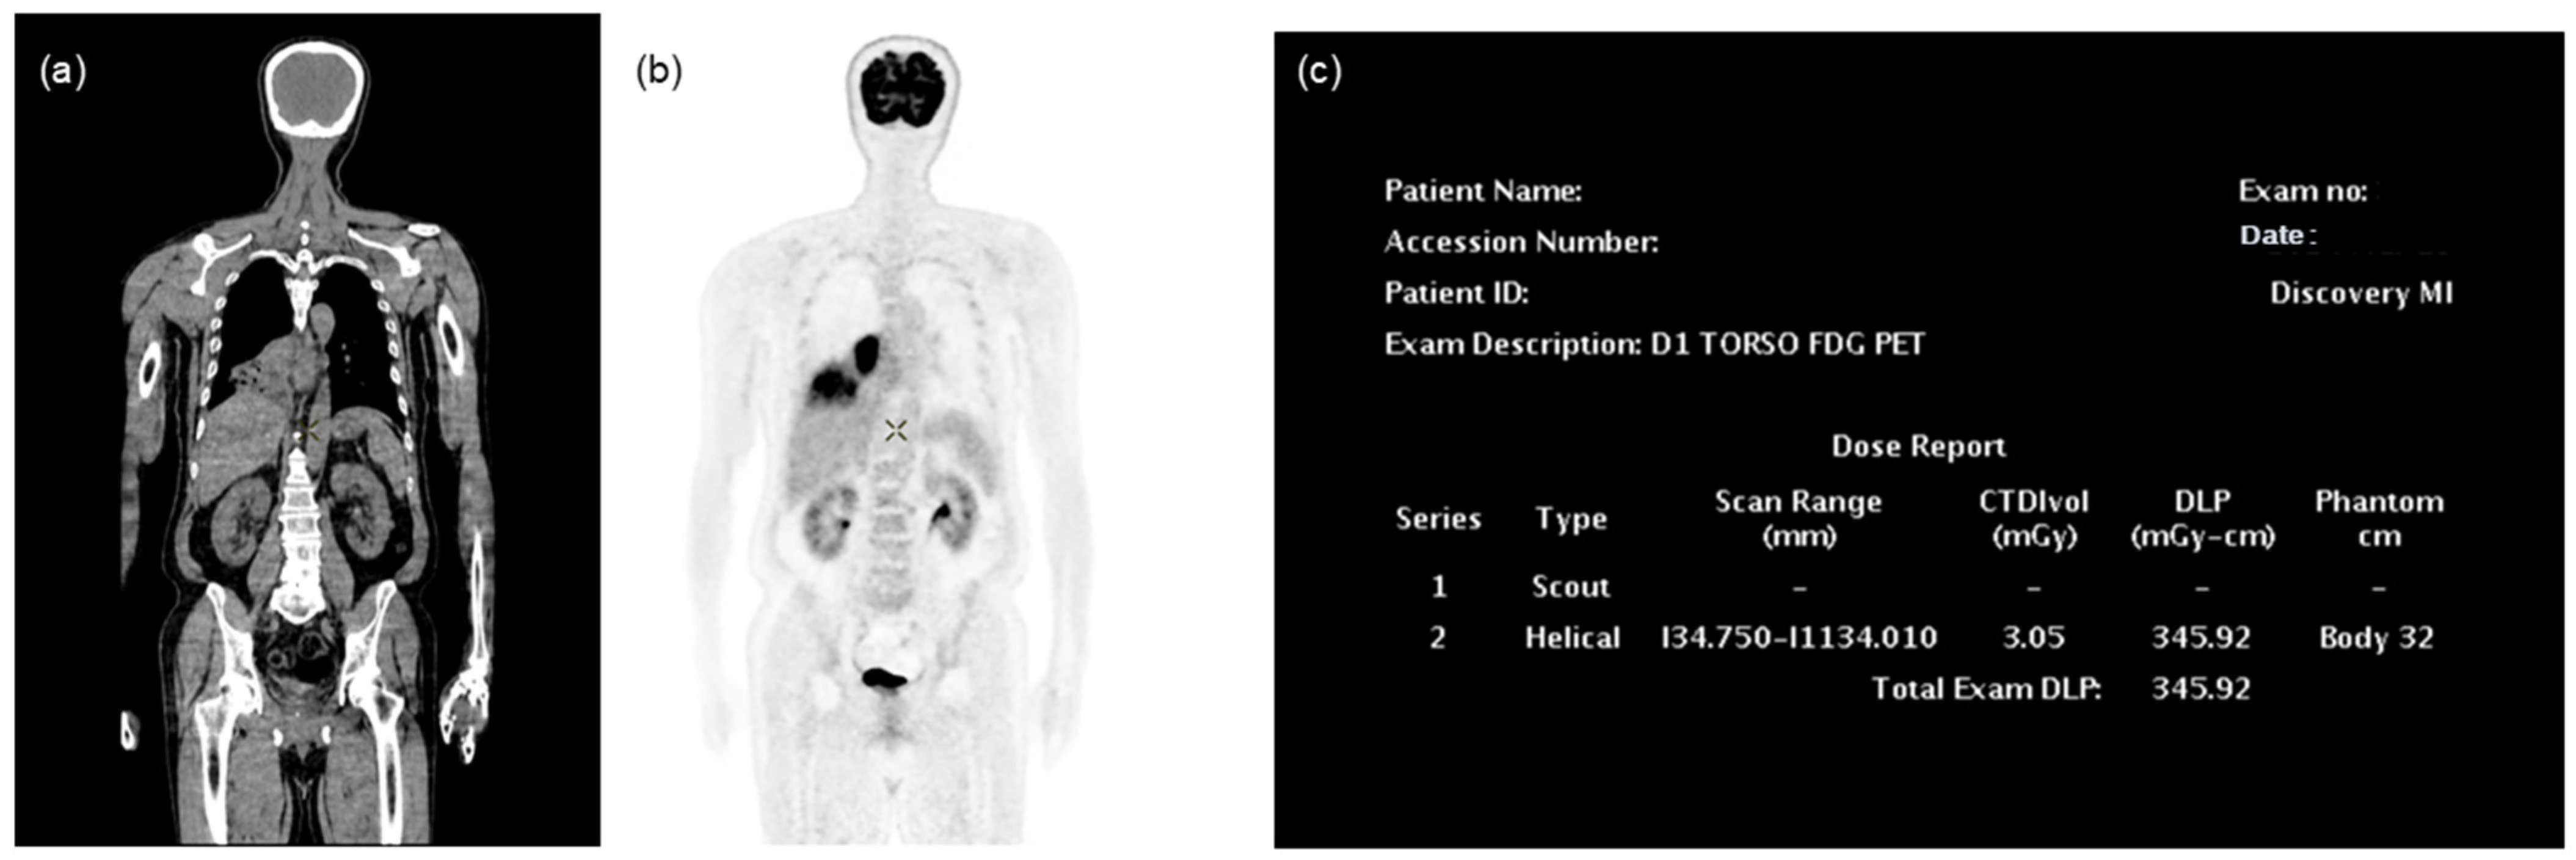

2.1. FDG PET/CT Protocol

2.2. Collection and Preprocessing of PET/CT Data